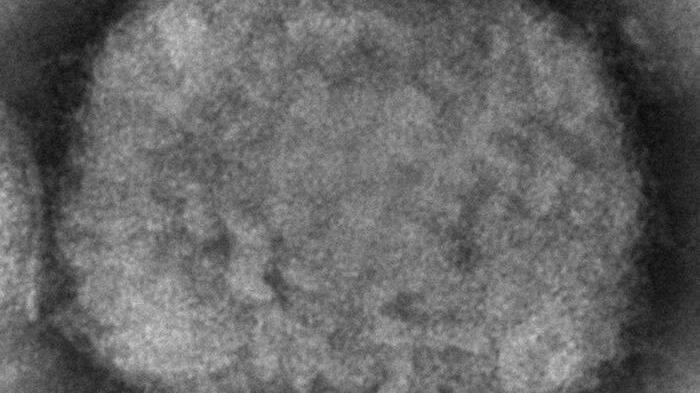

El subsecretario de Prevención y Promoción de la Salud, Hugo López-Gatell, confirmó a través de su cuenta oficial el segundo caso de la viruela del mono en México.

“Comparto que el InDRE ha confirmado un segundo caso de viruela símica en la Ciudad de México. El paciente se encuentra estable, recibe atención médica y se establecieron las medidas de aislamiento y control”, apuntó López-Gatell.

La Secretaría de Salud reportó hace dos semanas, el 29 de mayo de 2022, el primer caso de viruela del mono en México “importado” de un hombre de 50 años que venía de Nueva York y probablemente se ha contagiado en Holanda.

Asimismo, Secretaría de Salud Jalisco (SSJ), confirmó la sospecha de dos casos de viruela símica en un hombre de 40 años nacido en Canadá y residente en Puerto Vallarta y Una mujer de 23 años de edad originaria de Zapopan que convivió con extranjeros.